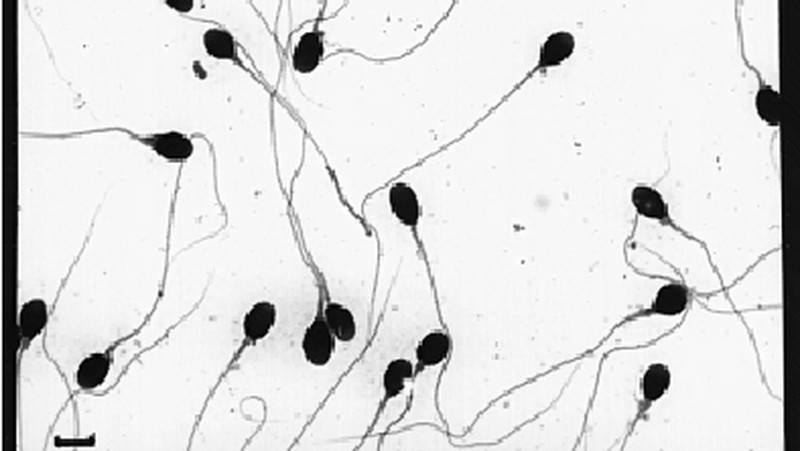

Sperma manusia yang normal seperti ini. Memiliki kepala lonjong bulat seperti telur dengan ekor yang panjang dan kuat. (Foto: Journal Molecular Human Reproduction/Leslie Goodwin)